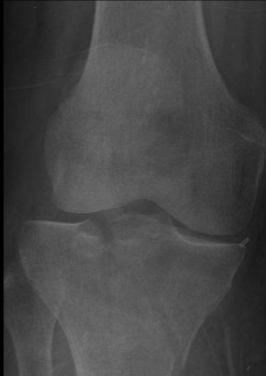

Q

A

Shatzker 5 y 6